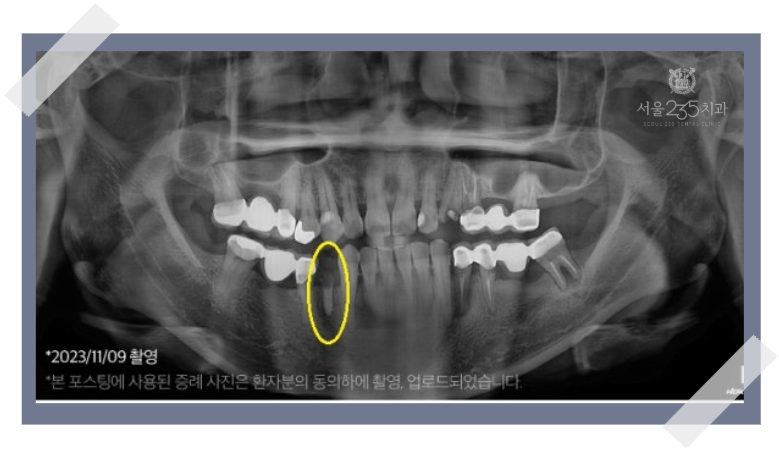

3. 심각한 염증을 동반한 경우

발치가 필요한 치아 주변으로 심각한 염증이 관찰되는 경우,

섣불리 남양주 임플란트를 진행할 수 없습니다.

오염된 땅에 새 건물을 지을 수 없듯,

염증 조직을 완벽하게 제거하고 건강한 잇몸 뼈가 재생될 환경을

만드는 것이 최우선입니다.

이러한 케이스는 아래와 같은 단계적 접근이 필요합니다.

(1) 문제 치아 발치 및 염증을 완벽하게 제거

(2) 잇몸과 뼈가 건강하게 아물 수 있도록 수개월의 회복기간 갖기

(3) 회복 후 부족한 뼈를 재건하는 뼈이식을 시행하고 계획된 위치에 임플란트 식립.

(때로는 뼈이식 후 다시 수개월을 기다려 뼈가 단단해진 것을 확인한 후 임플란트를 심기도 함)

이처럼 염증이 심했던 경우는 치료 기간이 길어질 수 밖에 없지만,

기초부터 탄탄히 다지는 이 과정을 거쳐야만 부작용 없는

남양주 임플란트를 기대할 수 있습니다.